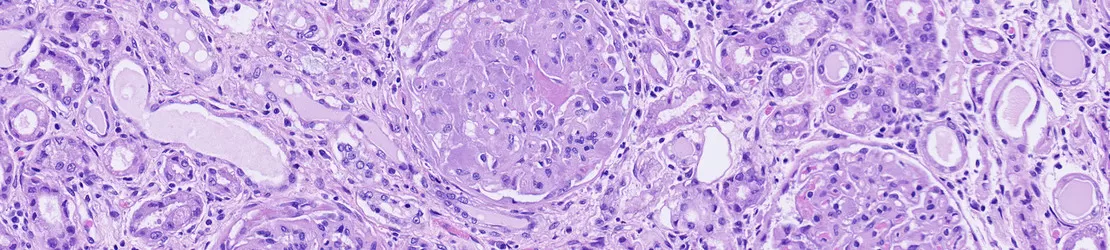

Imagine microscopica cu depunere de amiloid pe rinichi

• biopsia - o biopsie presupune prelevarea unei mici mostre de țesut pentru a fi examinată la microscop (depozitele de amiloid pot fi, adesea, observate în acest mod); biopsia poate fi efectuată pe diferite țesuturi, cum ar fi grăsimea (biopsie de tampon adipos), măduva osoasă sau țesuturi de organe, cum ar fi rinichiul sau ficatul, în funcție de simptome și de suspiciune;